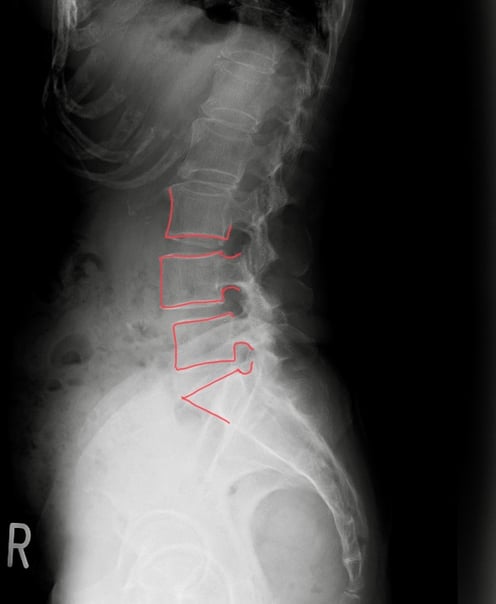

10年前に脊柱管狭窄症・腰椎すべり症と診断を受ける

確かに、画像上では第四腰椎のすべりを確認できるが、お身体の状態から、第五腰椎と仙骨間にかかる負担から起因している症状であると推測し、日常生活、歩行のポイントなどをアドバイスさせていただいた結果、早期に改善できたと考えます。